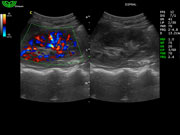

D7L40L 7.5МГц, линейный.

4.0МГц – 13.0 МГц. Применения: грудь, малые органы, нервы, сосуды, венозная катетеризация, мышцы и скелет, управление биопсией. |

Алгоритм снижения зернистости изображения (SPA)

- Программный расчет в реальном времени.

- Позволяет различать малейшие различия в тканях.

- Удаляет шум и делает нечеткие края более различимыми.

- Удаляет шум и делает изображение более похожим на анатомические стандарты.